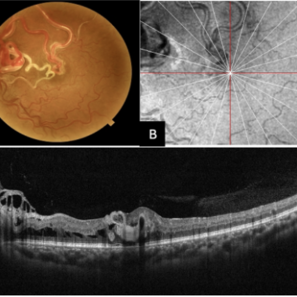

Multimodal Imaging of a Type 3 Retinal Racemose Hemangioma

Multimodal Imaging of a Type 3 Retinal Racemose Hemangioma

Sep 8 2024 by Maria Antonia Orrego

We present the case of a 33 year-old woman with visual loss of her left eye since childhood. Fundus examination revealed a retinal arteriovenous malformation with vessels originating from the optic nerve and extending to the fovea and equator, corresponding to a type 3 retinal racemose hemangioma (A). Infrared reflectance imaging confirmed findings described in funduscopy (B). Spectral domain optical coherence tomography shows dilated vessels in the internal and external retinal layers and adjacent intraretinal fluid (C).

Photographer: Dr. Maria Antonia Orrego V, Universidad CES, Clinica Clofán, Medellín, Colombia

Imaging device: Optovue Solix

Condition/keywords: arteriovenous malformation, multimodal imaging, racemose hemangioma, retinal arteriovenous malformations